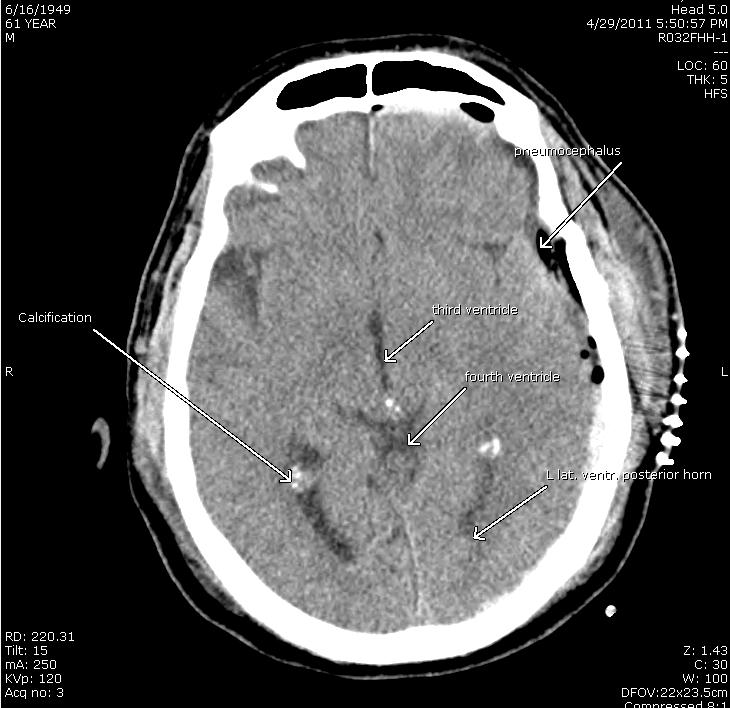

Brain Injury Diagnoses With Ct Or Cat Scans Jim Dodson Law